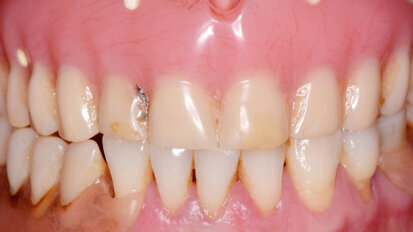

Retence získává nový význam